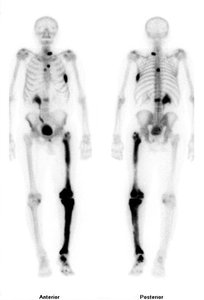

Radioactive isotopes are used in medical diagnostics (e.g., Tc-99 for heart and bone scans).

Radioactive isotopes are used in medical imaging and diagnostics.